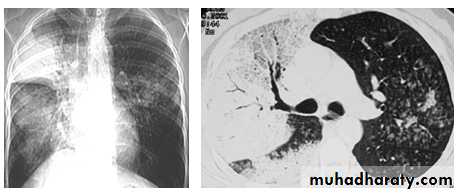

Pleural Effusion on Chest Radiographs.

Posteroanterior (A) and lateral (B) chest radiographs demonstrate the typical meniscoid appearance (arrows) in a patient with a left pleural effusion